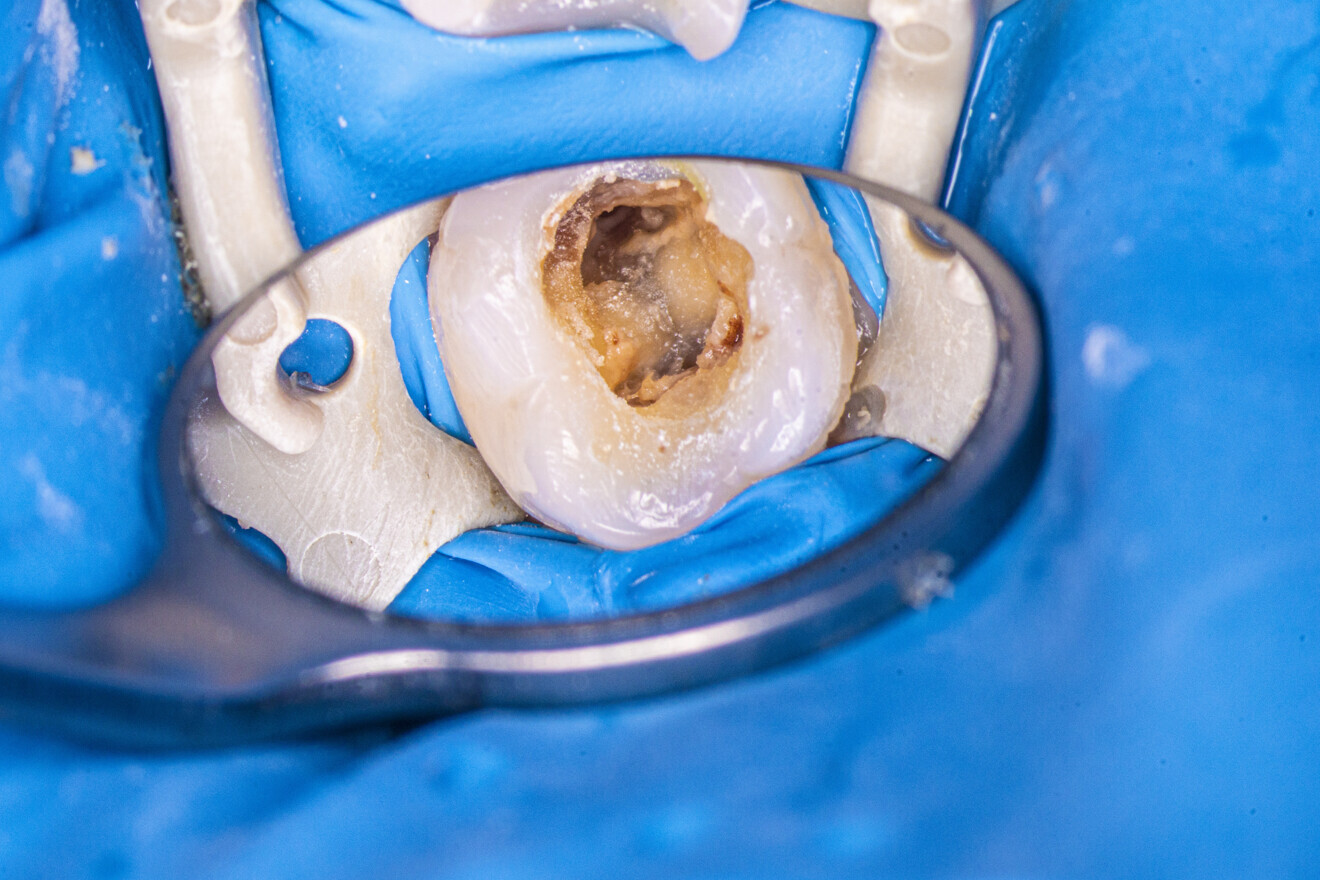

The patient was referred to the office for root canal retreatment of three teeth before prosthodontic treatment. One of these teeth was the mandibular left first molar. The CBCT scan revealed two radiolucent spaces around both roots (Fig. 26). Moreover, the periapical radiograph showed a broken file in the mesiobuccal canal (Fig. 27). After administering anaesthesia and placing a dental dam, the old restorations were removed, a temporary composite build-up was performed, and the tooth was sealed with flowable dental dam (Figs. 28 & 29). The old gutta-percha cones were removed from all the canals (Fig. 30).

After the removal of the gutta-percha and cleaning of the root canals, it was apparent that a large amount of the dentine had been removed from the orifice of the mesiobuccal canal (Fig. 31). Most probably, this had occurred during an attempt at removing the broken file in the previous treatment. Fortunately, there were no visible signs of perforation in the orifice. The damaged wall was sealed with composite resin (Fig. 32). Irrigation of the mesiobuccal canal with the AutoSWEEPS mode and sodium hypochlorite and inspection under 16× magnification revealed two pieces of the broken instruments (Fig. 33), complicating treatment. The tips of both files were visible, but both were also jammed. An attempt at removal with an ultrasonic file was ineffective, so the flat SWEEPS 300/20 fibre tip was used with the AutoSWEEPS mode at a power of 1.2 W. After a few minutes of irrigation with sodium hypochlorite and EDTA, both file pieces started to move a little, indicating that both were removable. Both pieces were retrieved with a lasso loop tool (BTR Pen, CERKAMED; Fig. 34). A periapical radiograph was performed to confirm that there were no more broken file pieces (Fig. 35).